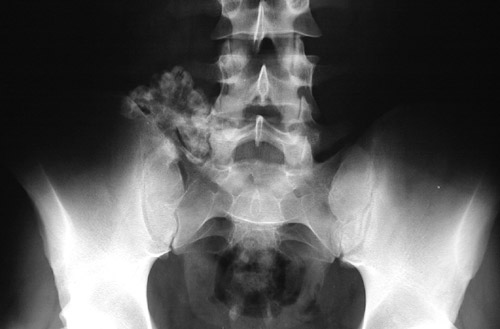

| The radiograph of the pelvis shown here demonstrates an osteochondroma projecting from the iliac wing. This is an unusual location, but the appearance of a projecting mass with calcification is characteristic for osteochondroma, which is more of a localized area of disordered bone growth than a true neoplasm. |